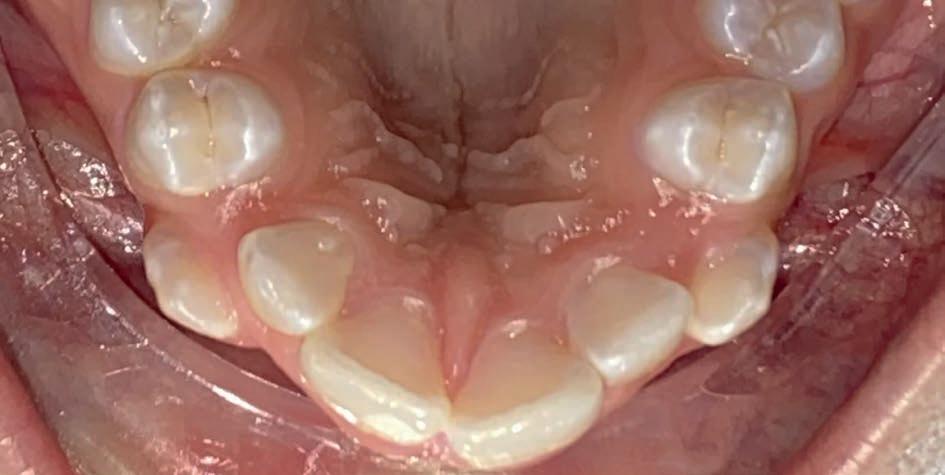

Casus: Blix – Ruimte creëren zonder extracties met D-gainer en Damon Ultima Blix (10 jaar) presenteerde zich met een klasse II-occlusie, smalle boven- en onderkaak en ruimtegebrek voor de doorbraak van de hoektanden en premolaren. Hoewel haar gezicht in balans was, zou zonder behandeling het gebrek aan ruimte toenemen en de diepe beet verder verergeren.

Behandeling in twee fasen

1. D-gainer & verbreding

Om extracties te voorkomen, werd gestart met een D-gainer. Dit is een methode met slotjes en veertjes waarmee de molaren gecontroleerd naar achteren worden verplaatst. Tegelijkertijd werd de tandboog verbreed – zonder buitenboordbeugel.

• Doel: ruimte creëren voor de hoektanden (13/23) zonder premolaren te verwijderen

• Duur: ongeveer 6 maanden

2. Vaste beugel (Damon Ultima)

Na voldoende ruimte werd gestart met de volledige vaste beugel in boven- en onderkaak. Hiermee werden de tandbogen uitgevlakt, de scheefstand gecorrigeerd en de tandbogen verbreed – met behoud van het natuurlijke profiel.

Resultaat

• Klasse I-occlusie

• Harmonieuze lachlijn en verbrede tandbogen

• Geen extracties

• Profiel en gezichtsbalans behouden

Retentie: Vaste spalk boven én onder, aangevuld met een nachtbeugel

“Door ruimte te creëren met een D-gainer in plaats van tanden te trekken, blijft het profiel natuurlijk en ontstaat een bredere, stabiele tandboog.”

voor